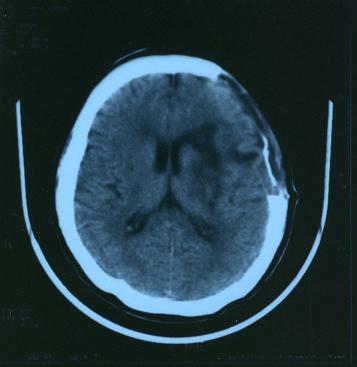

CT写真

平成15年2

月

4

日の写真

手術前の写真です。

白い部分が出血している箇所です。

出血した量が多く脳の中心の部分まで損傷を受けました。